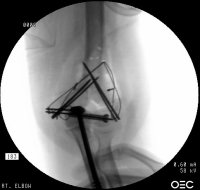

Initial fixation:

The fracture complex was assessed as the following, with central comminution - Posterior view:

The lateral epicondyle was found to have additional coronal comminution - Lateral view:

The medial column had a narrow proximal cortical strut remaining - medial view:

Taking all factors into account, including

• lateral column comminution - preventing solid plate fixation,

• the large screw occupying the central column could not be replaced by any screw small enough to engage a plate - preventing plate fixation,

the operating surgeon decided to achieve stability with triple tension band fixation and bone graft: